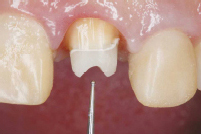

使用例

治療前

治療中

写真提供:坪田デンタルクリニック坪田有史先生